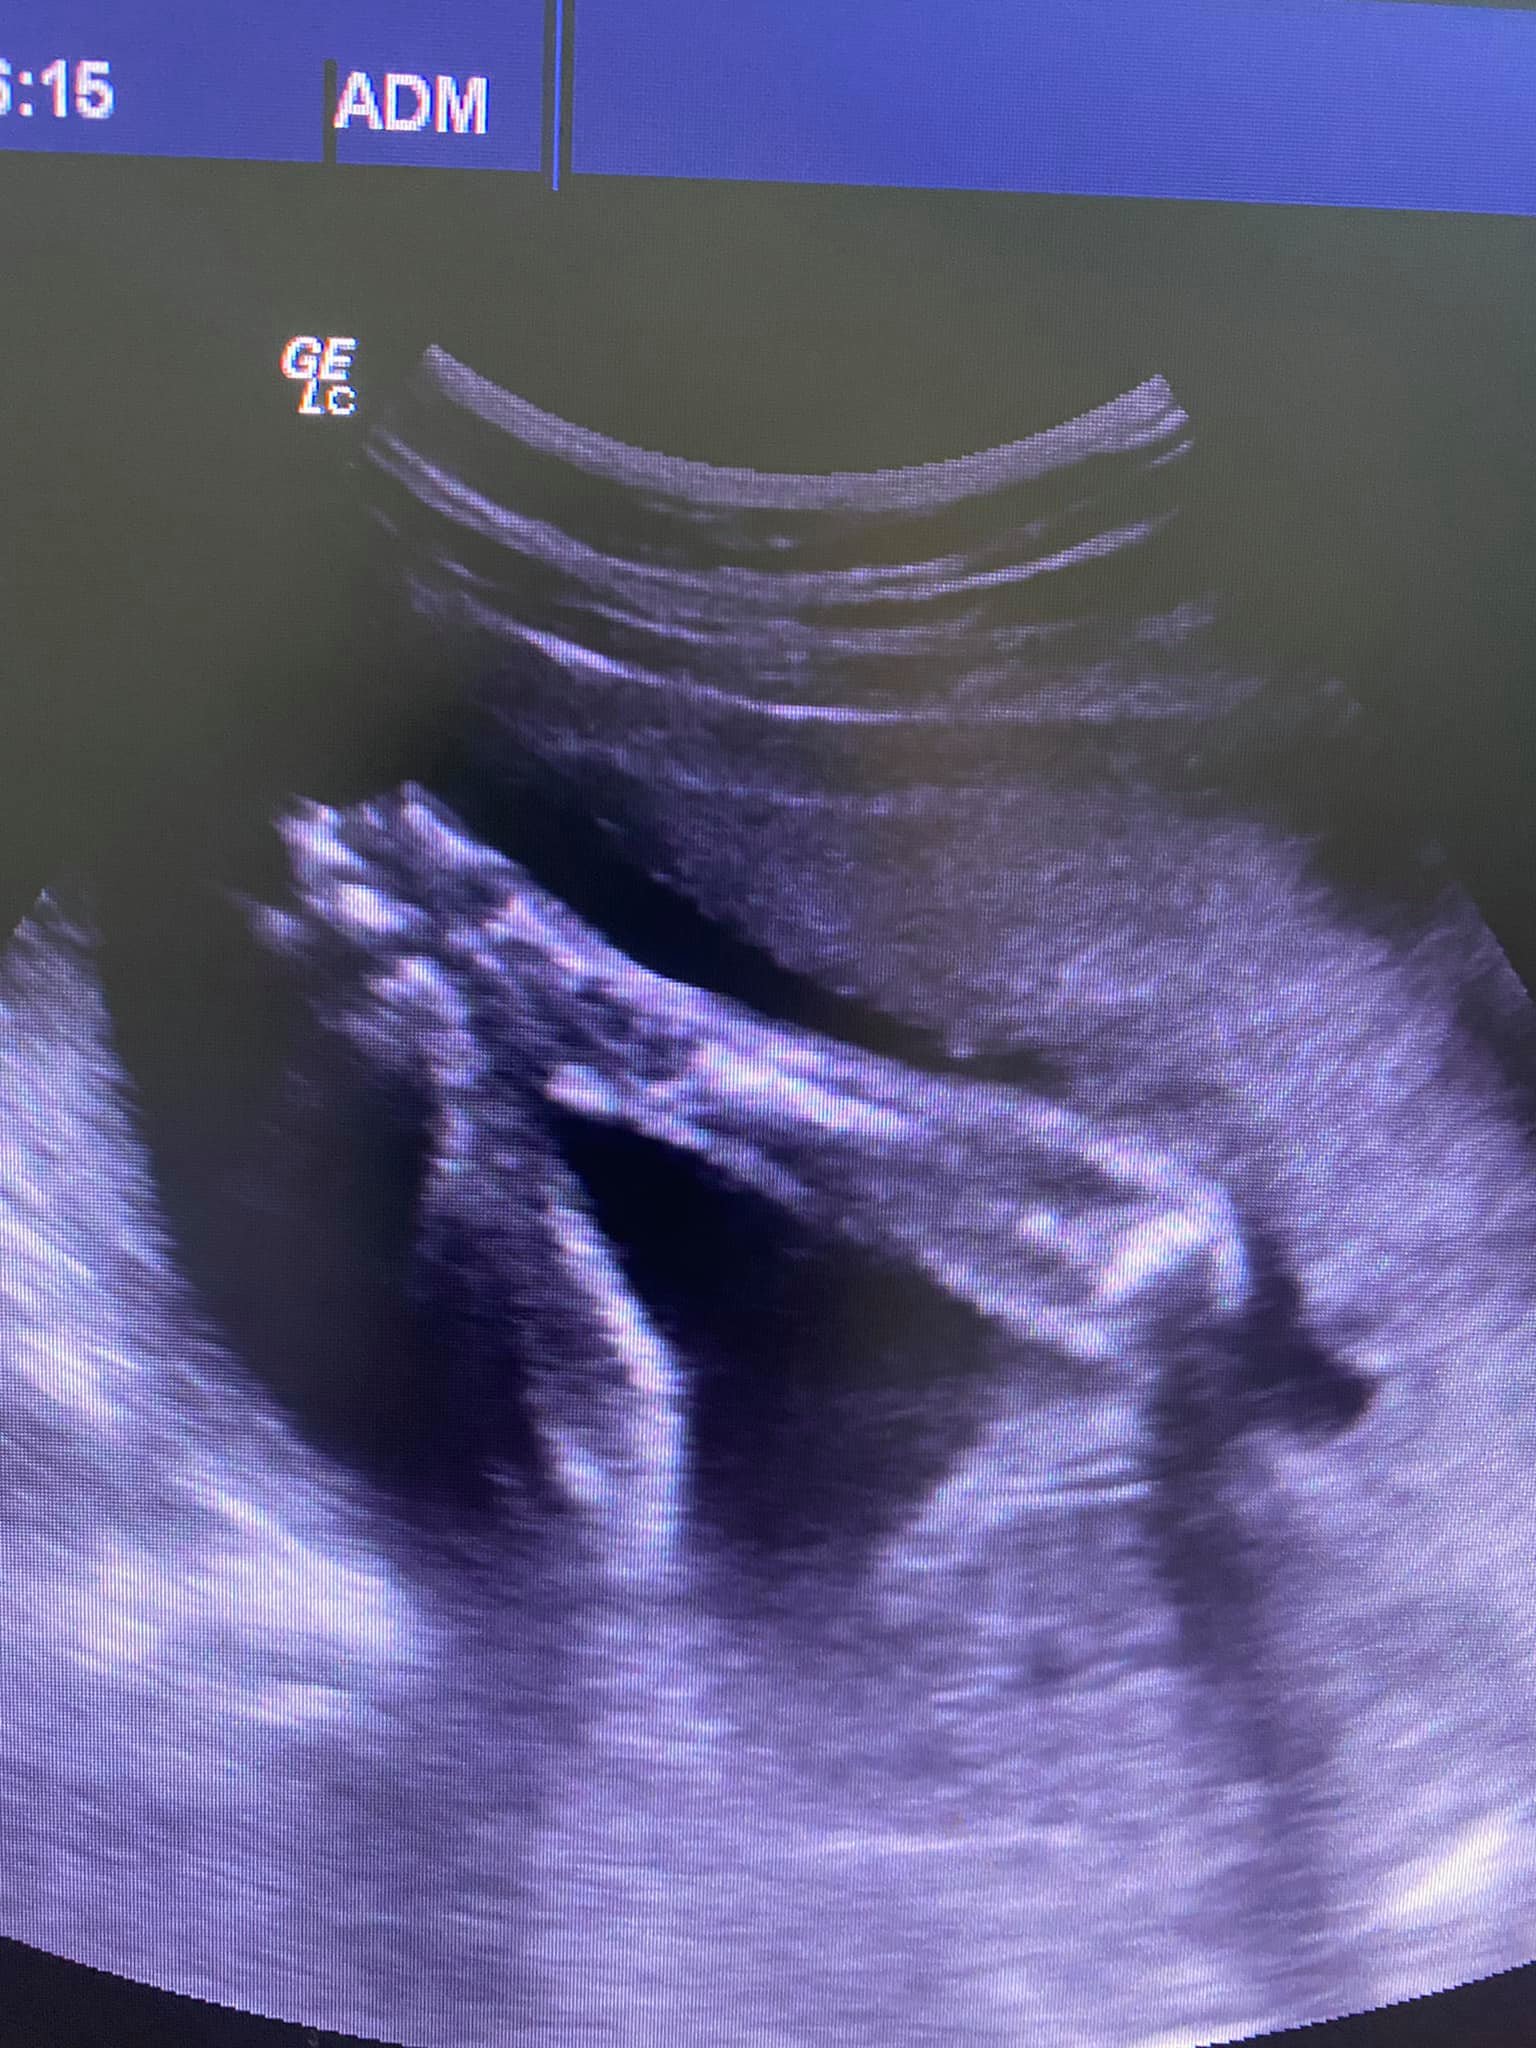

44-ամյա կինը 12 տարի անց մայրացել է․ բժշկուհին հրապարակել է ուլտրաձայնային հետազոտության լուսանկարը, որում փոքրիկը ձեռքերի խորհրդանշական պատկերով է

Fenix-Med բժշկական կենտրոնի բժիշկ Արմինե Միսակյանը լուսանկար է հրապարակել ֆեյսբուքում՝ կից գրառմամբ․